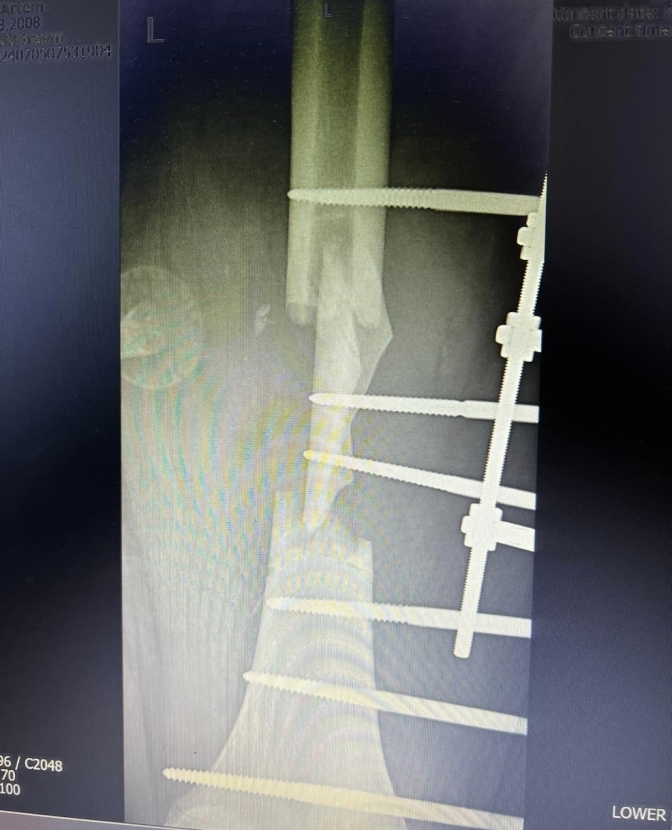

У Артема діагностували травматичний шок, великі рвані та скальповані рани лівого стегна і гомілки, відкриті багатоуламкові переломи лівої стегнової кістки та обох кісток лівої гомілки з множинними саднами та забоями кінцівок і тулуба.

У процесі клінічного та рентгенологічного обстеження було виявлено, що у дитини відсутня частина стегнової кістки довжиною 12 см, яка залишилася на місці ДТП. Тож родичі хлопця поїхали на місце події та знайшли елемент кістки. Тим часом, через 6 годин після госпіталізації, лікарі почали складне комбіноване втручання, зокрема накладення двох VAC-апаратів роздільно на ліве стегно та гомілку.

У процесі подальшого лікування Артему було зроблено ще три операції, зокрема вільна шкірна пластика дефектів стегна та гомілки повношарованими перфорованими клаптями.

Після демонтажу VAC-апаратів, Артем вертикалізований, ходить з милицями з дозованим навантаженням на уражену кінцівку, усі рани зажили, а пересаджені шкірні клапті прижились.

Артем вже пройшов один курс реабілітації у лікарні та вже виписаний додому. У подальшому хлопець ще буде проходити курси реабілітації у Клініці реабілітації, а процес лікування триватиме ще приблизно 3 місяці до повного зрощення кісток та демонтажу апаратів зовнішньої фіксації.